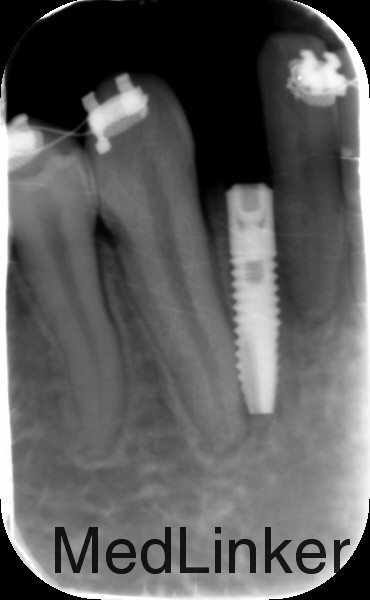

治疗:1、联合正畸科治疗,正畸科移动双侧中切牙至中线两侧后留出位置行种植治疗 2、常规消毒铺巾局部麻醉,切开翻瓣,植入Astra种植体3.0*8mm种植体两枚,严密缝合

多学科联合治疗是未来的趋势,这个病例患者先天缺牙,且间隙大,可先做正畸治疗腾出缺牙空间行种植治疗,种植治疗后已高基台保持间隙